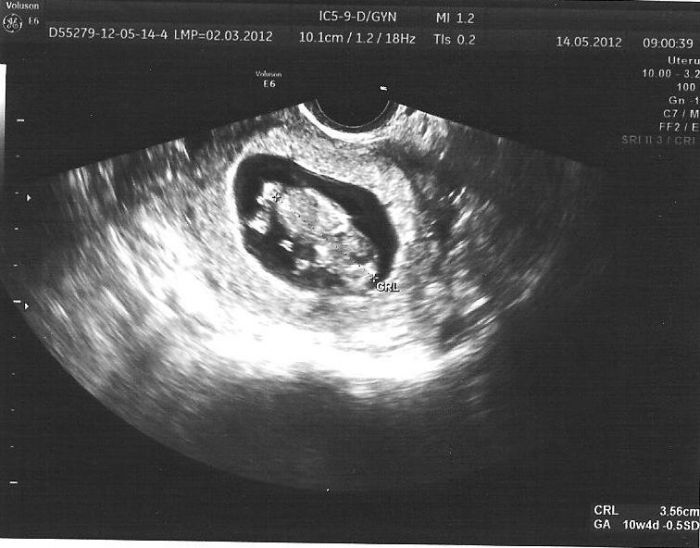

dlouho jsem tu nebyla a opět koukám jak nás tu přibívá. :-) Já jsem teď 12+3 termín máme zatím 7.12. S mimouškem jsme zvládli plánovanou dovču v Egyptě,samozřejmě po radě s doktorem a vše naprosto v pohodě :-) Příští týden jdeme na první genetiku,už se moc těším a doufám že nám řeknou jestli je to holčička nebo chlapeček.Snad to bude vidět.Přikládám foto z ultrazvuku něco po 10týdnu :-)